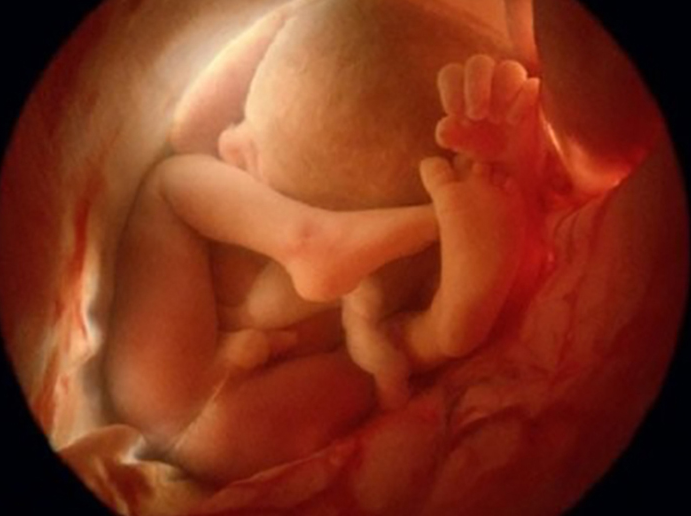

Siêu âm 4D là phương pháp siêu âm hiện đại, nâng cấp hơn so với phiên bản 2D, 3D trước đó. Nếu siêu âm 2D có hình ảnh mặt cắt theo không gian 2 chiều thì siêu âm 3D là hình ảnh thể hiện không gian 3 chiều với nhiều góc độ khác nhau. Siêu âm 4D là siêu âm gồm 3 chiều không gian và 1 chiều thời gian.

Với siêu âm 4D, mẹ bầu sẽ thấy em bé chuyển động như đang xem một đoạn video được ghi hình. Cụ thể, mẹ có thể thấy em bé đang làm gì, đôi khi bắt gặp bé đang mỉm cười, di chuyển tay, chân, mút ngón tay,...

Tương tự như siêu âm 2D, siêu âm 4D là phương pháp kiểm tra chẩn đoán về tình hình phát triển của thai nhi, phát hiện các dị tật bẩm sinh nếu có và đánh giá tình trạng sức khỏe của mẹ.